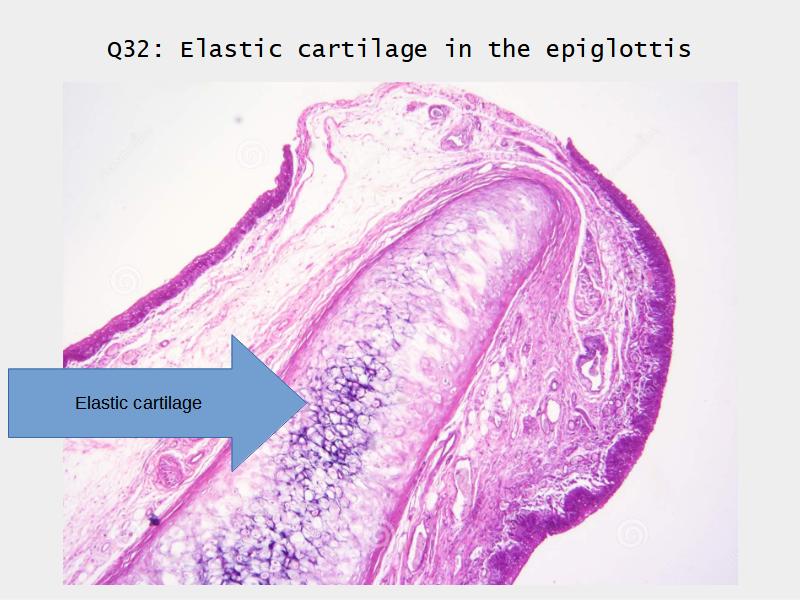

- Slide 111: Epiglottis

Epiglottis